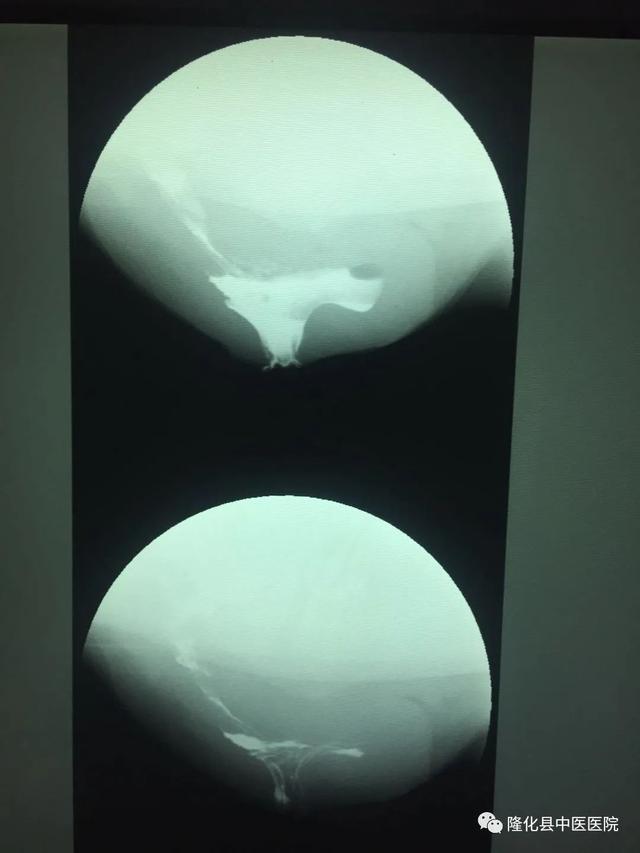

直肠排便造影检查新技术,通过向病人直肠注入造影剂,对病人“排便”时肛管直肠部位进行动、静态结合观察的检查方法。它能显示肛管直肠部位的功能性及器质性病变,为临床上便秘的诊断治疗提供依据,对诊断出口梗阻性便秘有着重要的临床意义,对手术方法选择有良好的指导作用,解决了患者去三甲医院预约排队检查的难题。